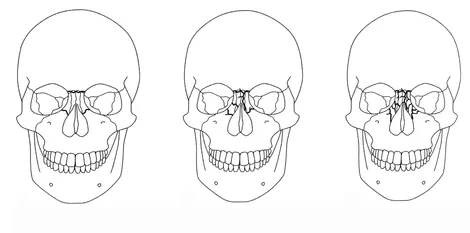

Existem vários tipos de fraturas que podem ocorrer no rosto e na mandíbula, muitas vezes resultantes de trauma facial. Aqui estão alguns dos tipos mais comuns de fraturas faciais:

Fraturas Nasais

Fratura Le Fort ou de Maxilar

Fratura Mandibular

Fratura de Zigoma

Fratura FNOE

Fratura Pan-faciais